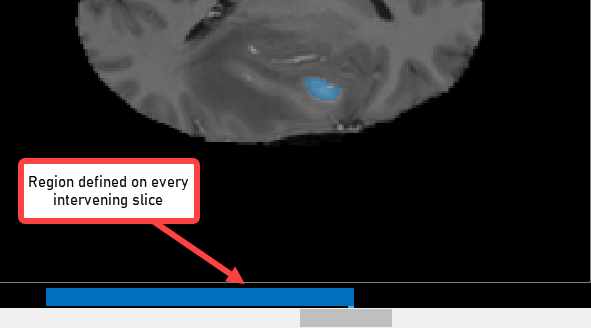

With the object defined on two slices, click Auto Interpolate. The app automatically defines the ROI on all the intervening slides. The app uses blue bars to indicate all the slices that have ROIs, which now appear as a solid bar from slice 35 to slice 88.